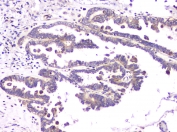

IHC staining of FFPE human esophageal squamous cancer with RAB11B antibody at 1ug/ml. HIER: boil tissue sections in pH6, 10mM citrate buffer, for 10-20 min and allow to cool before testing.